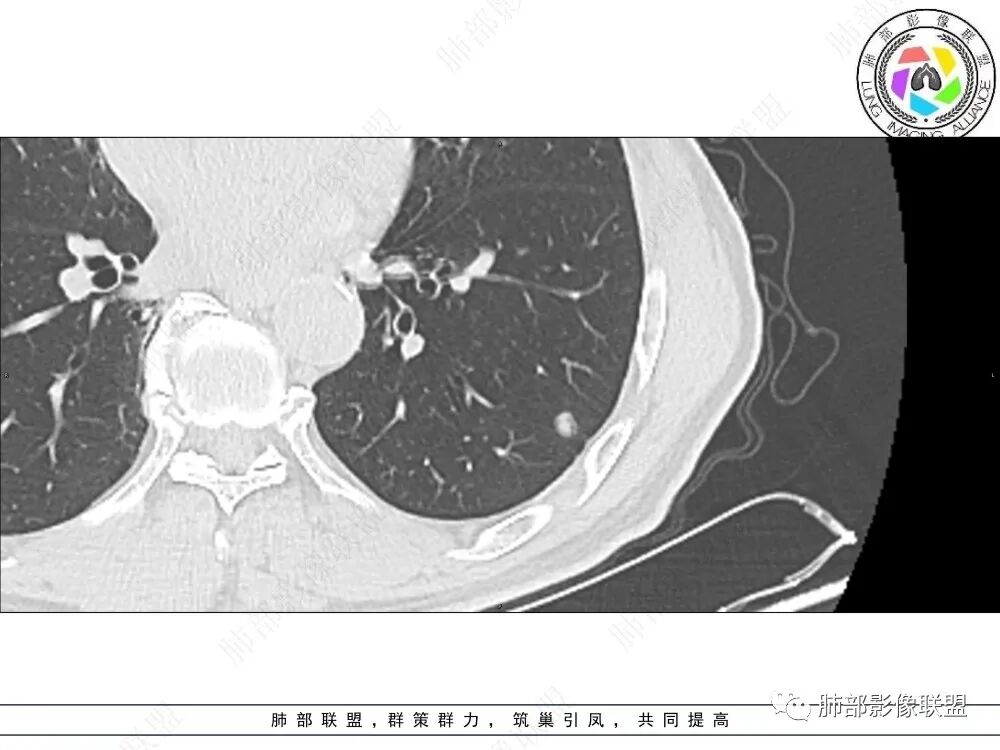

1、临床特点:中老年男性,间断左侧胸痛2年余,复发1月余,既往左肺上叶占位穿刺确认肺腺癌,未行手术治疗,给予两次射频消融术,术后定期复查,1月前患者出现左下胸部阵发性刺痛,无畏寒、发热、咳嗽等其他临床症状,门诊胸部CT提示:左肺下叶新发结节。

2、影像特点:左肺上叶尖后段病灶结合病史考虑消融术后改变,双肺下叶胸膜下可见多发大小不等的实性结节,周围似乎有晕,边缘平直为主,未见深分叶,部分可见邻近胸膜牵拉,张力不高,增强后呈轻中度强化。

3、总结:中老年男性,间断胸痛就诊,余无明显其他临床体征。既往肺癌病史,定期复查,一年左右双肺新发多发结节,常规需要鉴别炎性肉芽肿和肺癌转移。病灶以胸膜下为主,边界清楚,尽管转移是可以的,但混合磨玻璃时期腺癌相对惰性,短期内难以出现如此转移灶。况邻近胸膜牵拉,这在转移中也相对要少见。病灶多发,但没有新旧不等,没有树芽,病灶及时间线不支持继发性肺结核。病灶散在,胸膜下为主,周围可见少许晕征,部分病灶边缘比较平直,影像上较为符合隐球菌等肉芽肿性炎。

左肺上叶尖后段病灶消融术后改变:双肺下叶多发大小不等的实性结节,局部边缘平直,左肺下叶结节边缘不清,似见晕征,有原发病史且为新增,转移放前面,建议实验室检查除外隐球菌感染

病史时间:2018年8月12日确诊左肺上叶肺腺ca射频消融,2020年1月13日左肺下叶未见结节,2021年3月14日新发双肺下叶(视频图)见4枚实性小结节,边清,目测低强化,胸膜下的结节(3个)与胸膜粘连的特点,无收缩力,前后1年余倍增明显结节,多发,支持炎性肉芽肿结节,隐球菌荚膜抗原检查,其次与转移鉴别,非随机,位置仅双肺下叶,可能性小,建议左肺下叶后基底结节定位穿刺活检!